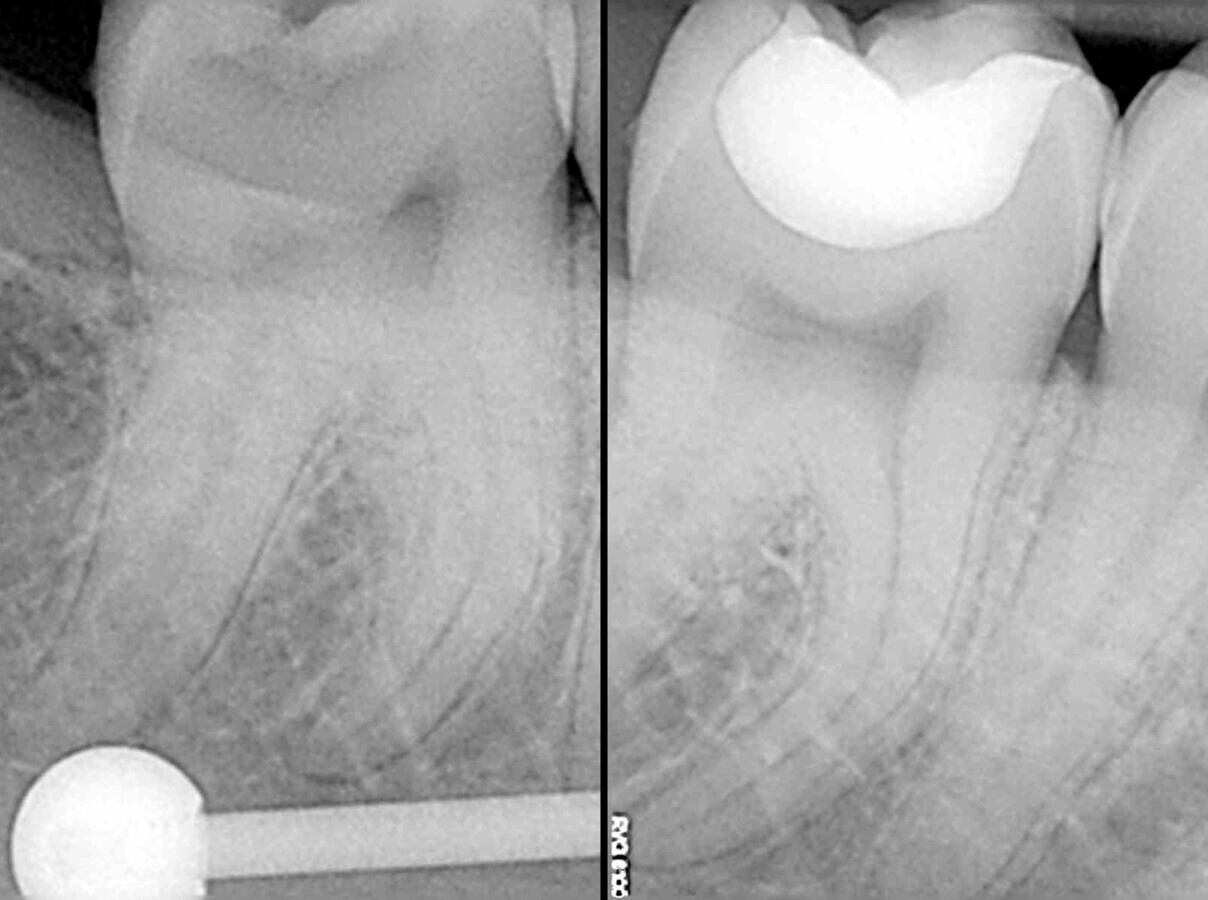

La comparación de las radiografías pre y postoperatorias muestra la calidad del tratamiento (Figura 31). Gracias a las excelentes propiedades tixotrópicas del composite termoviscoso, la restauración no contiene burbujas de aire. Además, se puede observar la uniformidad entre los tres composites utilizados en términos de radiopacidad y, en general, toda la restauración parece perfecta, sin ninguna transición visible entre el composite fluido, el composite bulk y el composite estético. Finalmente, la radiografía preoperatoria no mostró la extensión total de la lesión. Sólo durante el tratamiento se hizo evidente que era necesario realizar una preparación muy exhaustiva para eliminar por completo la estructura dental afectada. Para evitar molestias postoperatorias al paciente, se llevó a cabo una desensibilización tópica antes de la restauración con composite.

Figura 31. Radiografías pre y postoperatorias.